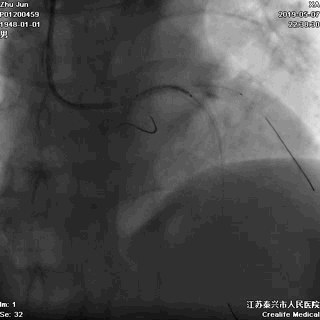

一、指引导管到位

---防止导管嵌顿和深插

主干开口病变,指引导管嵌顿或深插,就可能一招致命

游离一根导丝至升主动脉,防止导管深插

轻轻冒烟,证实指引导管到位

轻轻冒烟,大致了解前降支的情况

这一步相当重要。否则,无论是导管嵌顿,还是导管深插,稍不留意患者都有可能一招致命。